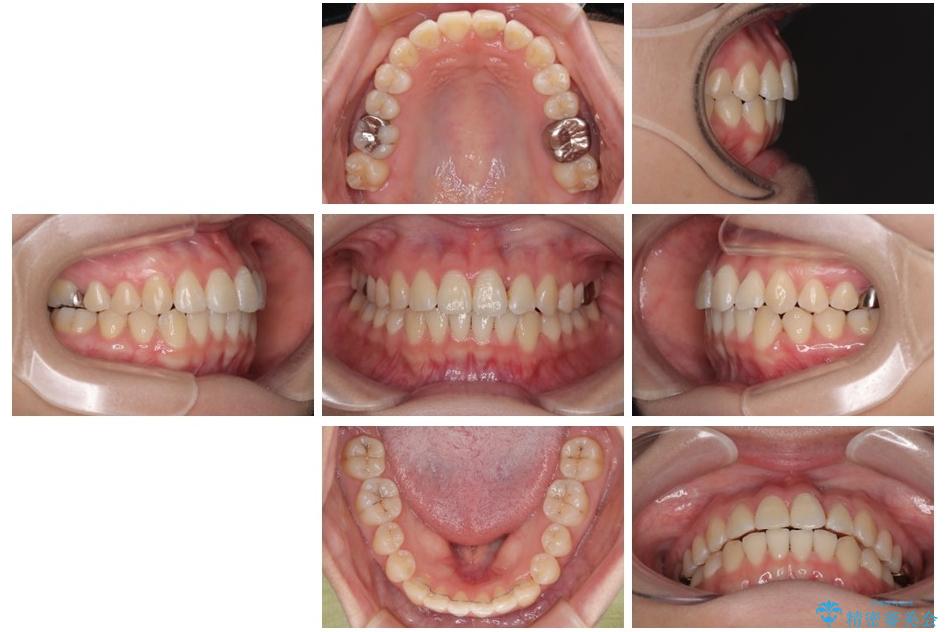

診察の結果、上下の前歯部に**叢生(そうせい/歯のガタガタ・重なり)**が認められました。

特に上の前歯にはねじれや重なりがあり、審美的にも清掃性にも影響している状態でした。

治療方法としては、装置の目立ちにくさと費用面のバランスを考慮して、プラスチック製のクリアブラケットとメタルワイヤーを組み合わせた矯正装置を使用することにしました。

また、上顎前歯の重なっていた部分にはむし歯が見つかり、治療中に適切な処置を行っています。

矯正治療期間はわずか10か月と、比較的短期間で終了しました。

前歯のデコボコがなくなり、見た目の印象が大きく変わっただけでなく、歯磨きがしやすくなり、むし歯や歯周病のリスクが大きく減少しました。

治療後

• 前歯のねじれ・ガタガタを10か月で改善!20代女性の矯正治療|クリアブラケットでむし歯になりにくい歯並びへ改善 治療後画像